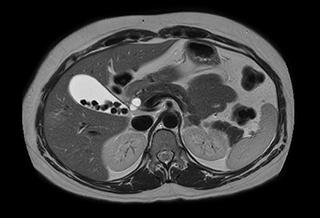

Abdominal MRI without contrast agent

Using mDIXON provides excellent fat saturation uniformity. No artifacts seen at the edges in these images, while these were quite commonly seen with eTHRIVE on our previous system. Note also the high resolution.

Ingenia Ambition, 3D breath hold, FOV 370 mm, voxels 1.51 x 1.58 x 4.0 mm, 120 slices, scan time 19.6 sec.